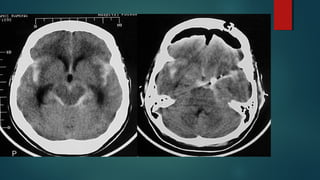

Este documento es el programa para un taller de imágenes del curso de emergencia 2015 impartido por el Dr. Víctor Delgado. El taller se centra en el uso de imágenes médicas para el diagnóstico y tratamiento de pacientes en coma traumático según la base de datos de Marshall. El Dr. Delgado es el único instructor repetido a lo largo del documento.